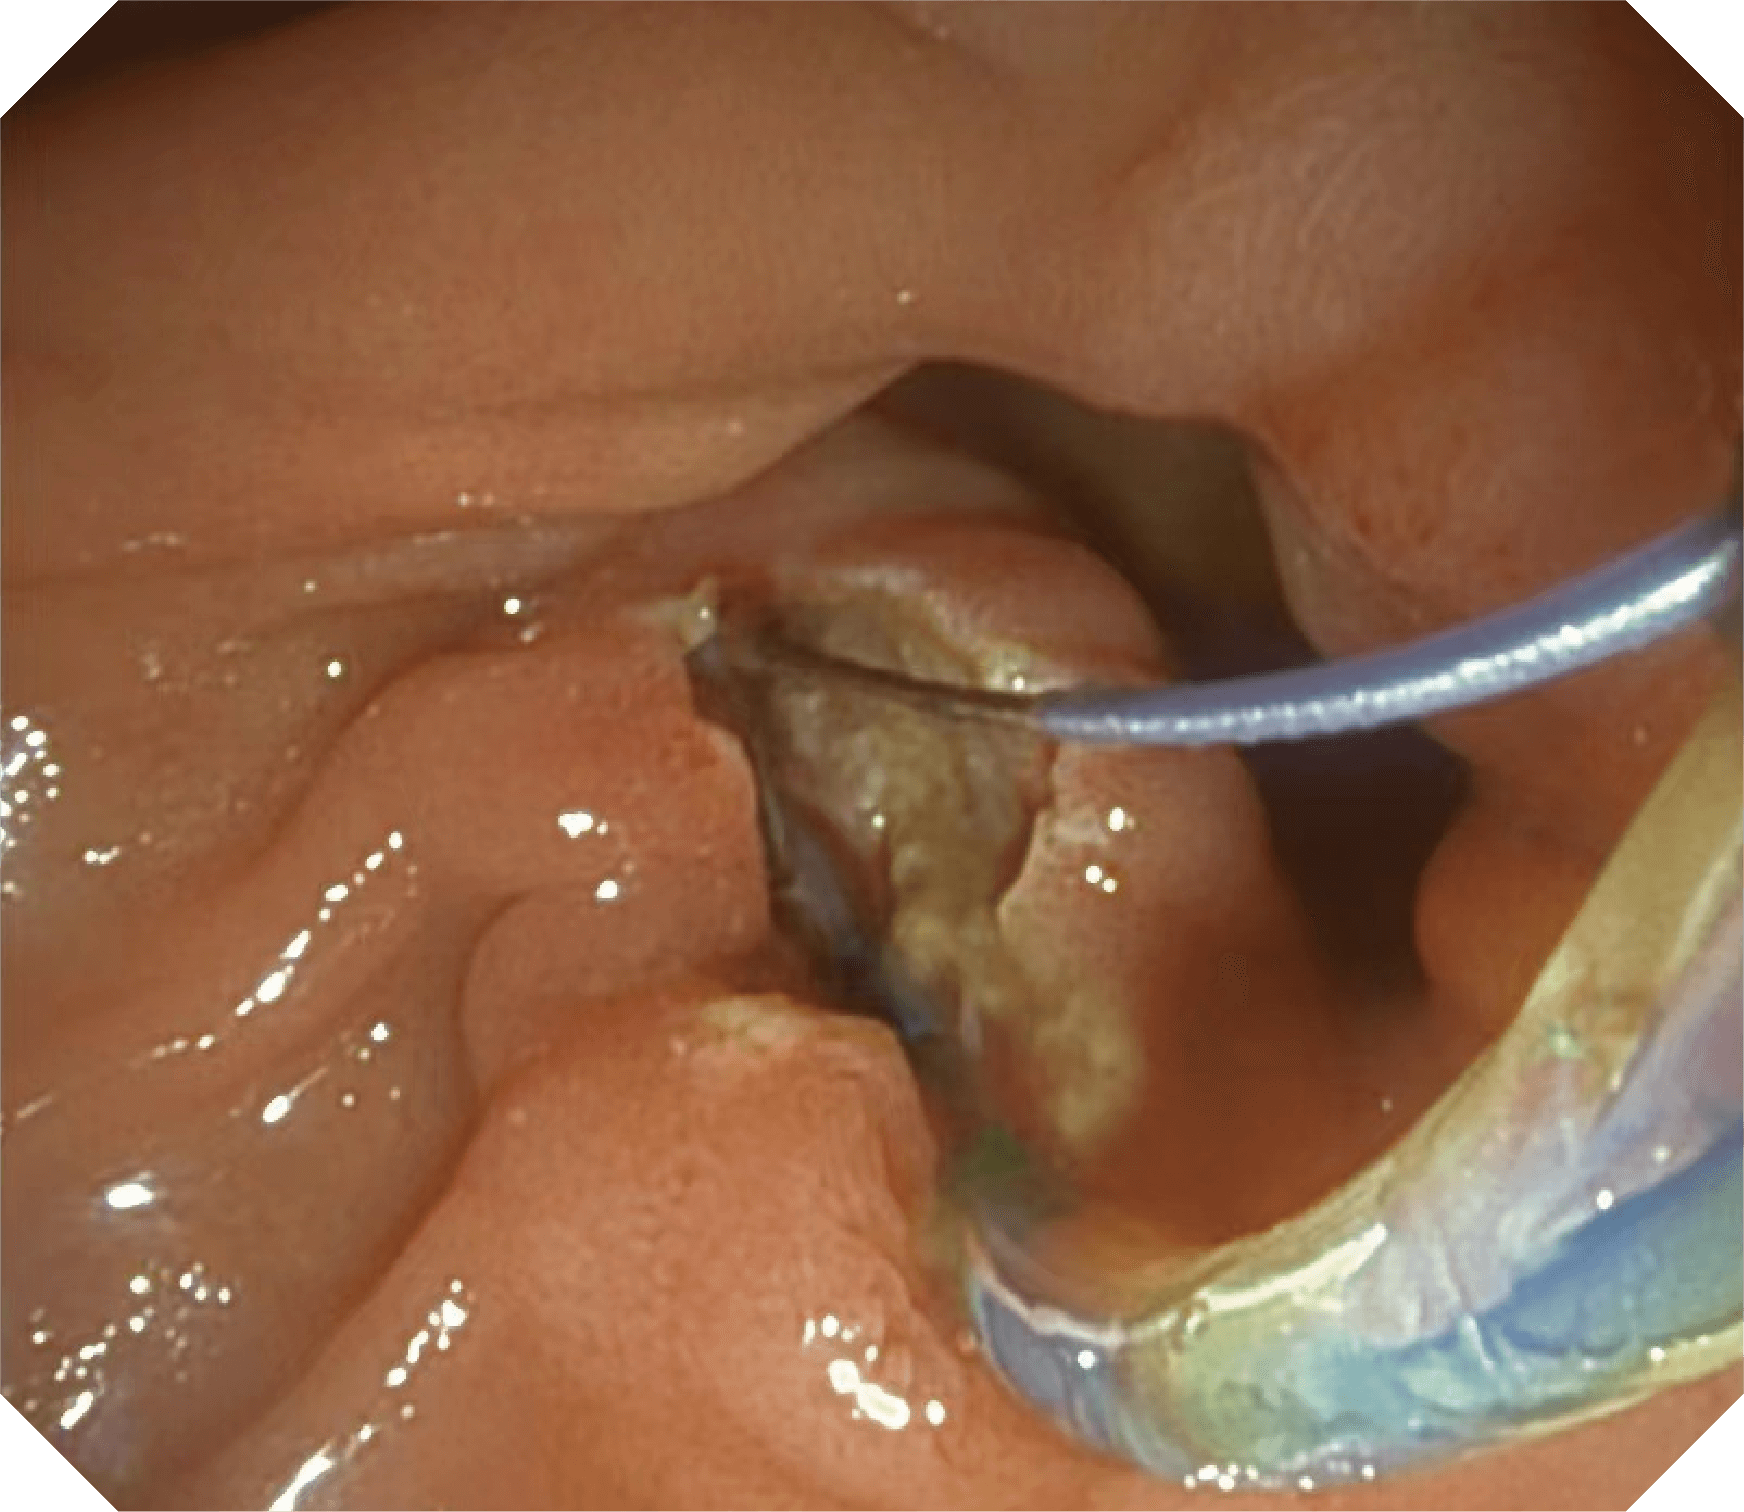

优异的手术器械抬举性

当切开刀伸出视野外时,导向面引导其回归视野